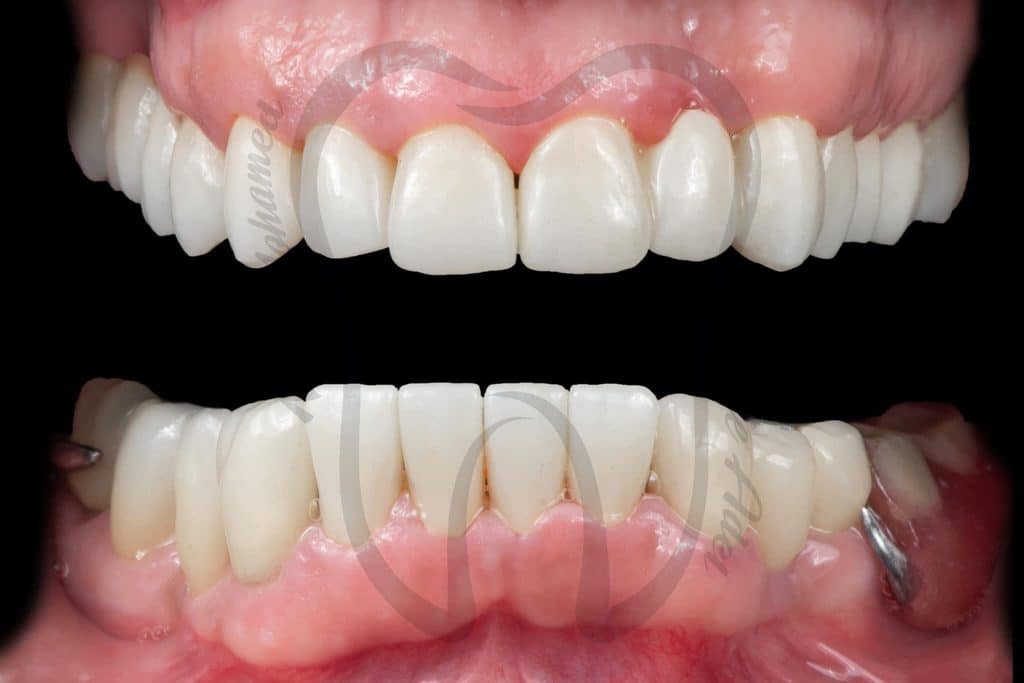

Graduation Case 🎓🎓

5th year student, PUA, Egypt

This case has been done together with my partner Dr Mai Marzouk

Our treatment plan included:

📌 10 Extractions

📌Full Mouth scaling and Root planing

📌 12 Endodontic treatment

📌 6 Post and Core

📌 Full Mouth Composite Restoration

📌 20 Unit Zirconium

📌 5 Unit PFM

📌 Lower Arch Class I Metallic RPD